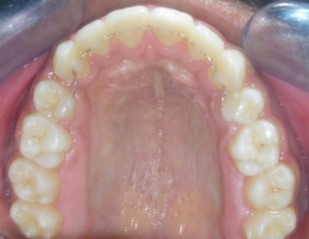

Intraoral assessment. (Figure 1d,Figure 1e,Figure 1f,Figure 1g,Figure 1h).

Figure 1g.Pre-treatment intra-oral-Upper occlusal

Pre-treatment intra-oral-Upper occlusal

The maxillary arch was V-shaped with severely proclined and rotated maxillary incisors with a palatally placed 12. The mandibular arch was U-shaped with severe crowding of mandibular incisors, with 43 partially erupted and buccally placed with transpositioned 42 and 43, with 42 mesiolingually rotated, 33 distolingually rotated and 34 distolingually rotated and buccally placed.

Severe increase in overjet and deep bite were both observed. The maxillary midline coincided with the skeletal midline but the mandibular midline was shifted to the right side by 1 mm. Bilateral maxillary posterior crossbite was also observed. On right side the molar relation was Class I and on the left side it was Class II. The canine relation was Class II on the left side and the curve of Spee was increased.